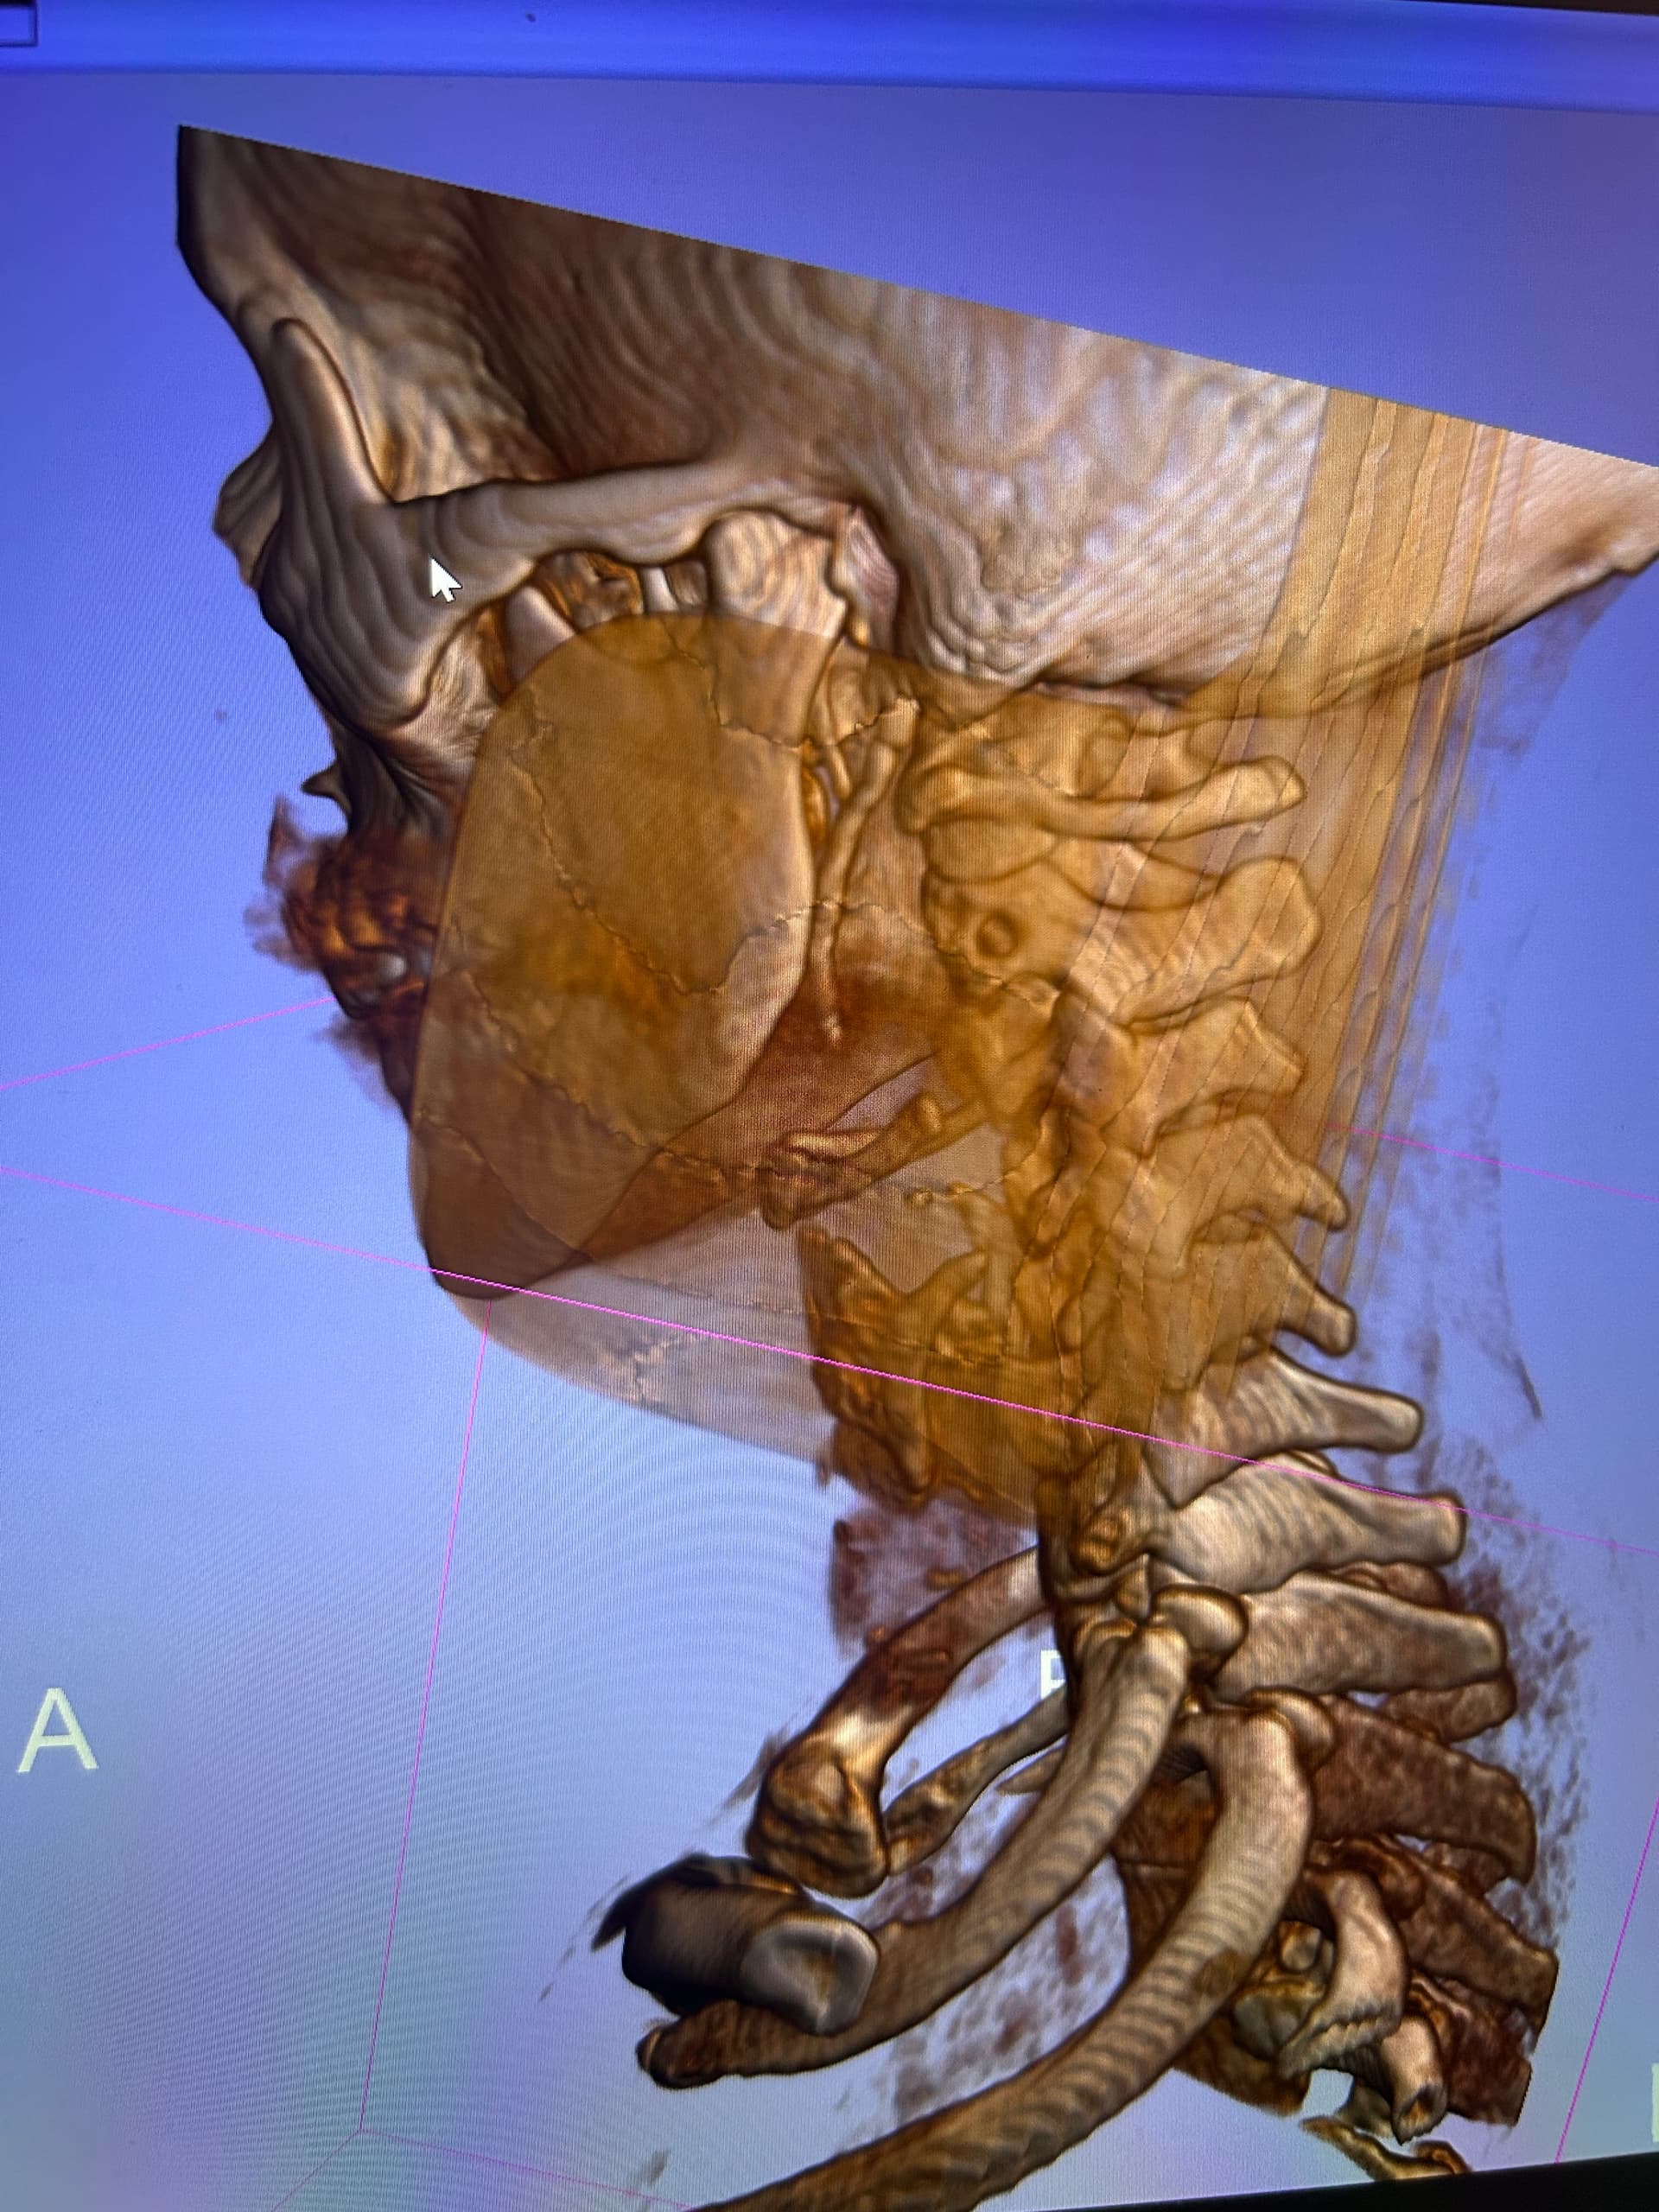

Hi @SeekingInfo knowing the length of the calcified ligaments is something, but seeing it in 3d just gives you a better picture of just how long they are and also the shape. If you can find the axial slice that @TML has mentioned previously then he can give you an idea with regards possible vascular compression between you styloids/ligaments and your C1 vertebrae.

Looking at your 3D images, your styloid on the left is completely calcified with the ligament very close to the C1 process, and looks pretty thick at the top, so I think would need to be removed at the skull base to stop IJV compression. On the right your styloid looks very long, plus extra calcified ligament at the end, again, it’s very close to the C1 and wide at the top. Your hyoid processes look quite thick, and also your thyroid cartilage looks pretty chunky…

I’m sorry that I can’t do labels, but on your left side, to the left of your styloid at the side of your jaw it looks like there’s something calcified, curved back towards the styloid process- I don’t know what that could be, I’ve never seen that before!

So I think looking at these images, it does change what you do next & which doctor you see, I do think that you need to get a consultation with one of the VES doctors, like Dr Nakaji, Dr Hepwort or Dr Costantino. So not as simple as you were hoping for :hugs: